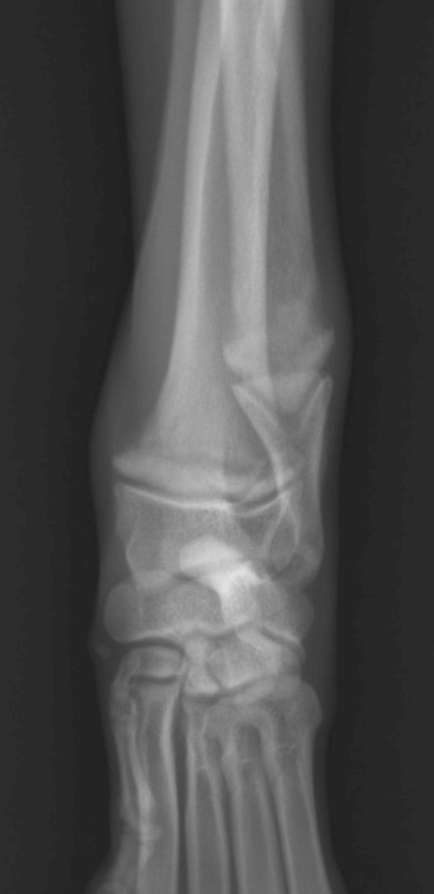

- L'examen radiographique, qui est crucial pour confirmer le diagnostic.

Les radiographies révèlent des signes pathognomoniques, notamment une ligne radiotransparente dans la métaphyse, parallèle à une zone étroite de densité accrue immédiatement adjacente à la physe. Il est important de noter que ces changements radiographiques peuvent ne pas être visibles avant 48 à 72 heures après l'apparition des premiers signes cliniques.Dans les stades plus avancés, on peut observer une prolifération périostée et endostée, ainsi qu'un élargissement excessif des métaphyses, créant un aspect caractéristique en "collerette" osseuse.Le diagnostic différentiel doit inclure l'hyperparathyroïdie nutritionnelle secondaire, la polyarthrite septique, les traumatismes, les noyaux cartilagineux retenus et l'ostéopathie hypertrophique.

Sclérose au niveau de la métaphyse du radius et de l'ulna

Mise en évidence d'une ligne radio-transparente irrégulière en regard de la métaphyse, longeant le cartilage de croissance et séparée de celui-ci par une bande radio-opaque.